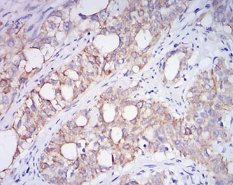

IHC    1/200 - 1/1000